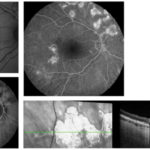

Presentazione e gestione di un caso di coroidite serpiginosa TB correlata

figg_5